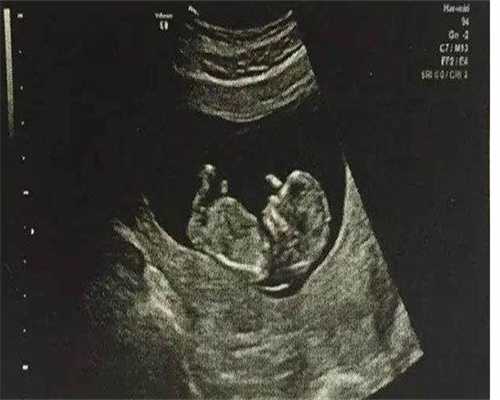

5、抽血验孕:一般来说,胚胎进入子宫腔3~4天后才能着床,但胚胎着床时间受个体差异影响,有的病人胚胎着床较晚。所以,为了提高验孕的准确性,医生通常建议病人在移植后14天到医院进行抽血检查。如果成功怀孕,14天后仍需做B超检查,排除宫外孕。